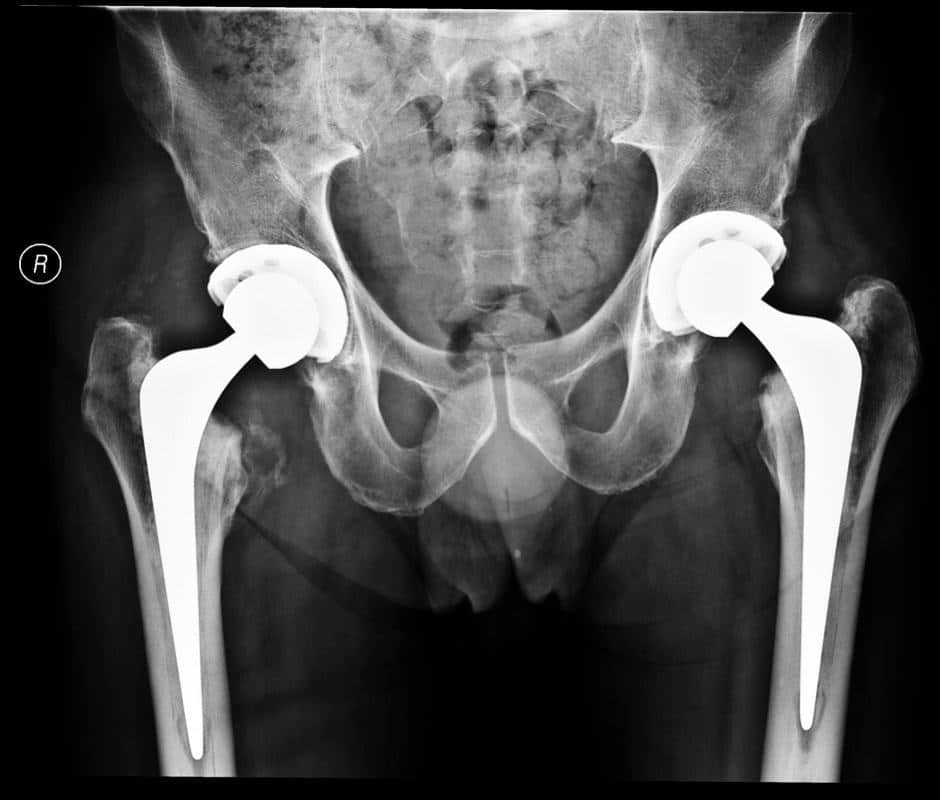

from www.markedmondson.co.uk

Hip Replacement Surgery Mark Edmondson Consultant Orthopaedic Surgeon